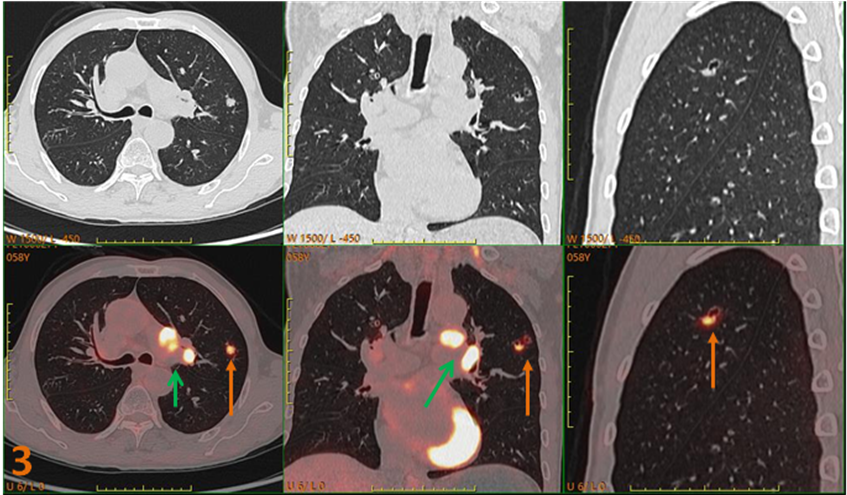

為明確原發(fā)灶行PET-CT進(jìn)一步檢查(圖3、4)。PET/CT示:左肺上葉不規(guī)則囊性灶(SUVmax約5.3),左肺門、主動脈弓下高代謝病變(SUVmax約12.1);診斷為左肺上葉癌并多發(fā)轉(zhuǎn)移。

圖3、4. 左肺上葉不規(guī)則囊性灶(黃箭),SUVmax約5.3;左肺門、主動脈弓下高代謝病變(綠箭)SUVmax約12.1。